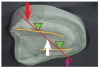

Consider a scenario in which the remaining bone in an edentulous lower arch has resorbed, medially and inferiorly. Visualize each ridge crest as a fulcrum, represented by the green triangles (Figure 9). Starting outside a fulcrum on one ridge crest, extend a line (represented in orange) to the other ridge crest past the ridge crest fulcrum on the other side. A downward force, represented by the white arrow, applied inside the two fulcrums pushes the line against both dental ridges. Force (red arrow) applied lateral to either fulcrum will cause the line to separate from the fulcrum on the opposite side (blue arrow). A similar situation exists in a resorbed upper ridge (Figure 10).

Limit contact to the posterior central fossae inside the yellow line.

Figure 9

Figure 10